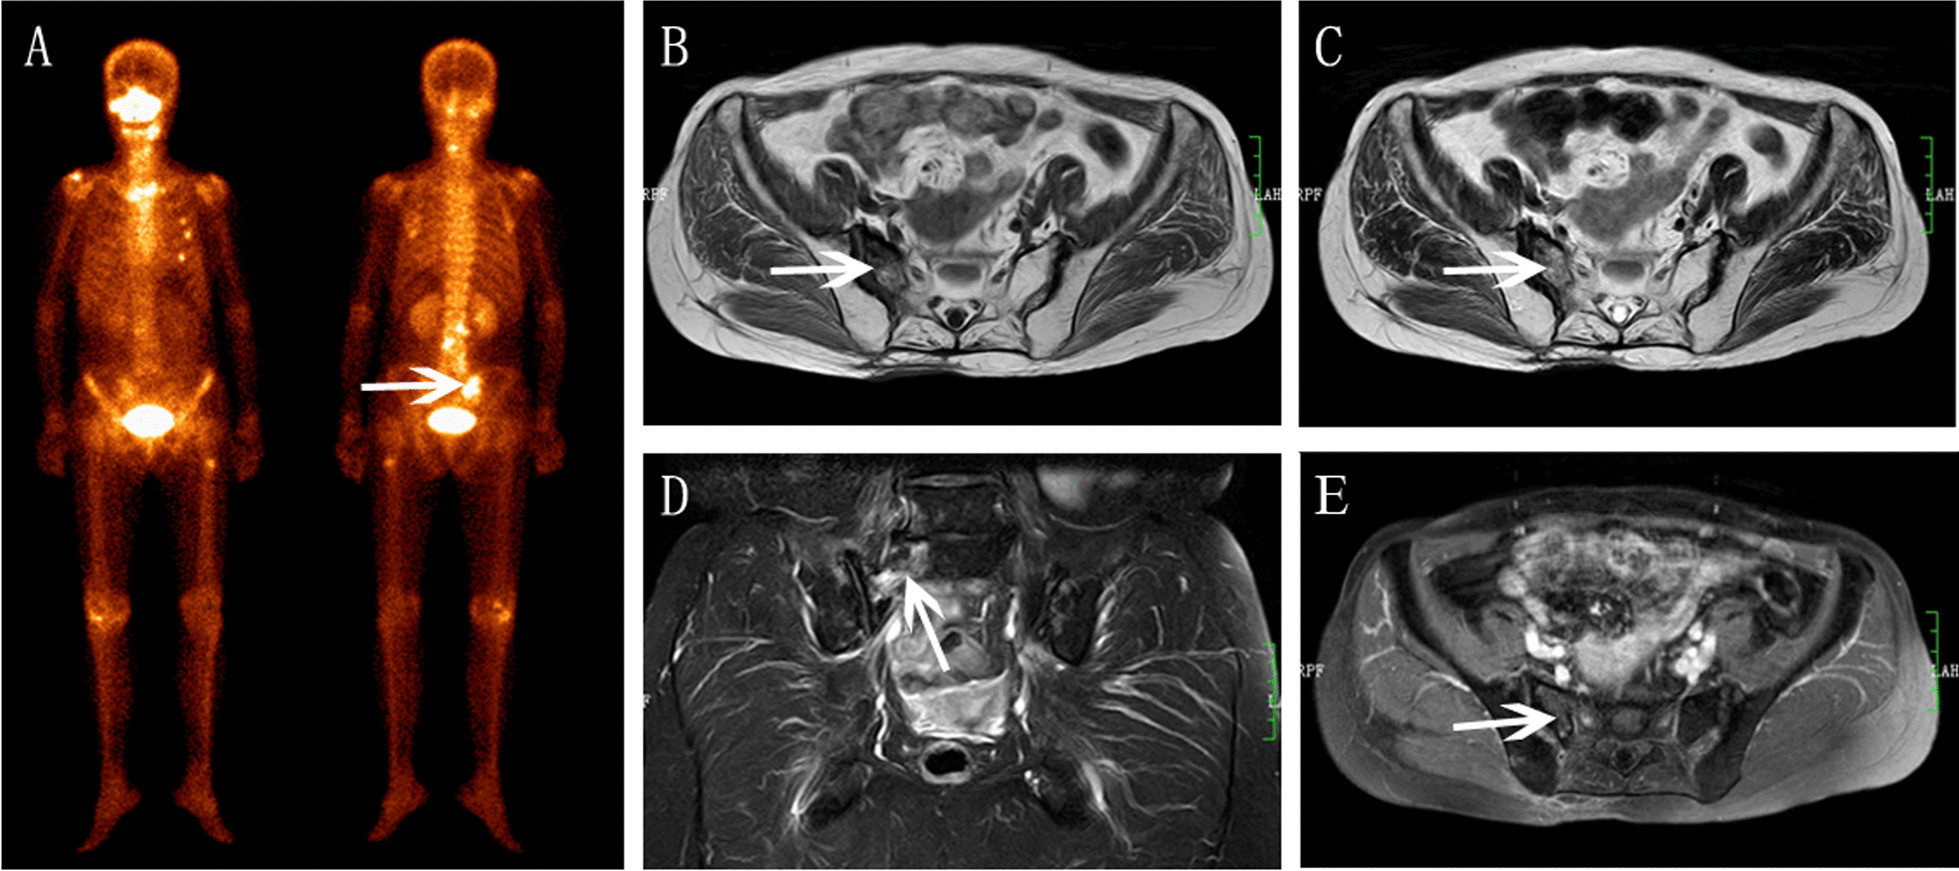

Fig.1.

Right SIF in a 58-year-old woman with cervical cancer after radiotherapy. A BS showed right sacrum increased accumulation (arrow). B Axial T1WI showed hypointensity. C Axial T2WI showed moderate hyperintensity. D Coronal FS-T2WI showed severe bone marrow edema and diagonal fracture line (arrow). E Axial enhanced T1WI showed mild contrast enhancement